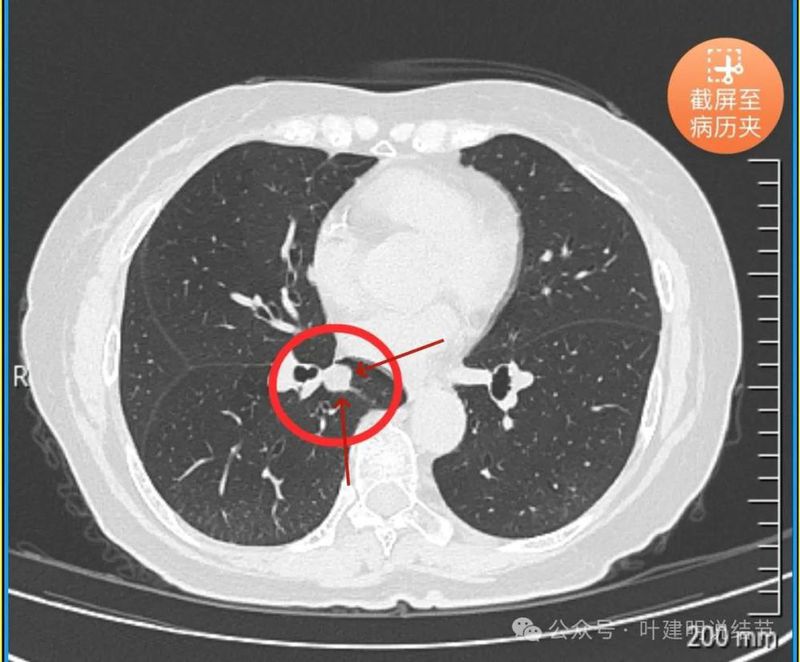

没有侵犯邻近支气管。

边缘光滑,分叶不明显。

上图这个层面感觉病灶与肺血管之间没有明显间隙,似像侵犯或愈着的样子。

结节边缘区域与血管之间又有间隙了的。

下肺静脉水平,病灶基本没有了。